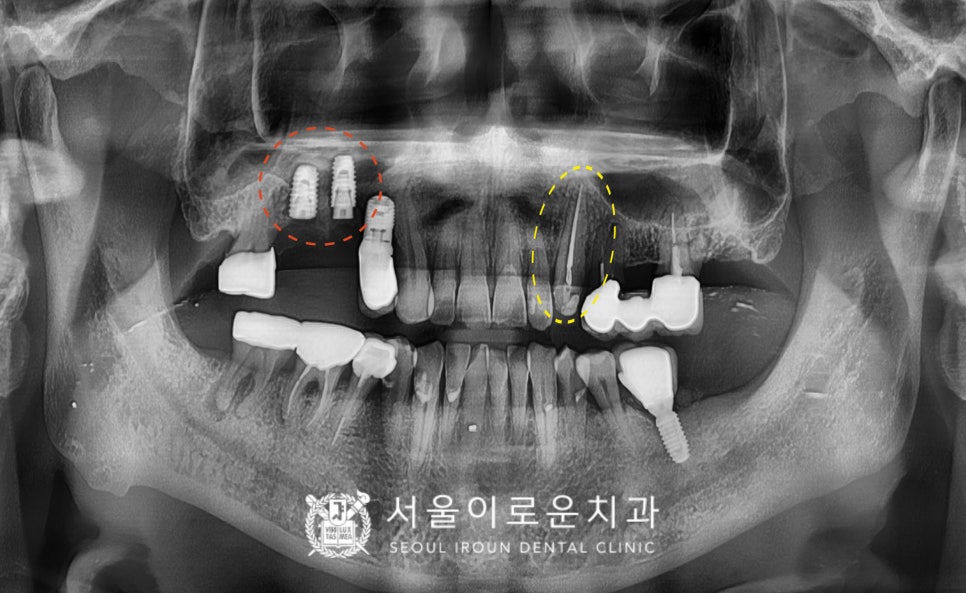

위턱 오른쪽의 임플란트가 잇몸뼈와

단단하게 결합되기를 기다리는 동안

위턱 왼쪽 송곳니(#23)의

크라운 제작을 위한

인상채득을 진행하였으며,

그리고 임플란트 식립 후 4개월 뒤

보철 과정을 진행하였답니다.

그리고 바로 뒤에

위턱 오른쪽 두 번째 큰 어금니(#17)는

기본 크라운 제거 후 평가해 보았더니

살려 쓸 수 있다고 판단하여

임플란트와 같이 보철물 제작을 위한

인상채득을 진행하였습니다.

그리고 맞춤형 지대주를 체결하여

자연치아와 강도가 가장 유사하고

심미적인 지르코니아 크라운으로

임플란트 보철물과 크라운 보철물을

마무리해 드렸습니다.

위턱의 치.료가 마무리 된 후

아래턱 오른쪽 두 번째 큰 어금니(#47)의

치료도 진행하였는데요.

치료를 위해 기존 크라운을 제거하고

충치를 깔끔하게 제거 후

뿌리 끝까지 신경치료를

꼼꼼하게 마무리 해드렸답니다.

신경치료 후 기존 증.상들이

사라지신 것을 확인한 후

크라운 수복을 위한 인상채득 후

위턱과 마찬가지로 지르코니아 보철물로

수복을 마무리해 드렸습니다.

임플란트 / 크라운 수복

신경치료 후 크라운 수복을

모두 마무리 한 모습입니다.